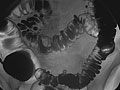

- In a single-contrast study, the colon is filled with barium. This outlines the intestine and shows large abnormalities.

- In an air-contrast or double-contrast study, the colon is first filled with barium, and then the barium is drained out. This leaves only a thin layer of barium on the wall of the colon. The colon is then filled with air. This provides a detailed view of the inner surface of the colon. It makes it easier to see narrowed areas (strictures), diverticula, and swelling.